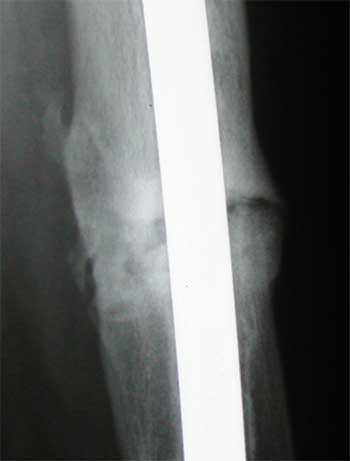

Lateral Views. Note bone growing in the muscle (top left). Let's all hope it goes away.